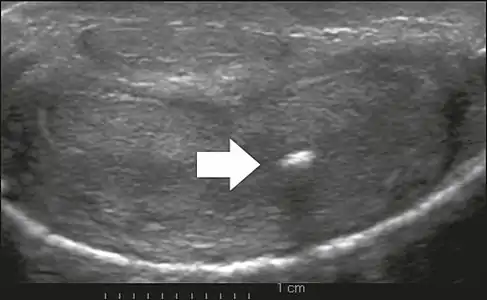

On penile ultrasonography, the typical appearance is hyperechoic focal thickening of the tunica albuginea. Due to associated calcifications, the imaging of patients with Peyronie's disease shows acoustic shadowing, as illustrated in figures below. Less common findings, attributed to earlier stages of the disease (still mild fibrosis), are hypoechoic lesions with focal thickening of the paracavernous tissues, echoic focal thickening of the tunica without posterior acoustic shadowing, retractile isoechoic lesions with posterior attenuation of the beam, and focal loss of the continuity of the tunica albuginea. In the Doppler study, increased flow around the plaques can suggest inflammatory activity and the absence of flow can suggest disease stability. Ultrasound is useful for the identification of lesions and to determine their relationship with the neurovascular bundle. Individuals with Peyronie's disease can present with erectile dysfunction, often related to venous leakage, due to insufficient drainage at the site of the plaque. Although plaques are more common on the dorsum of the penis, they can also be seen on the ventral face, lateral face, or septum.[13]

Transverse ultrasound of the penis, in a ventral view, in the middle portion of the penis. Note the echoic image with posterior acoustic shadowing, corresponding to calcification (arrow), in the left corpus cavernosum.[13]